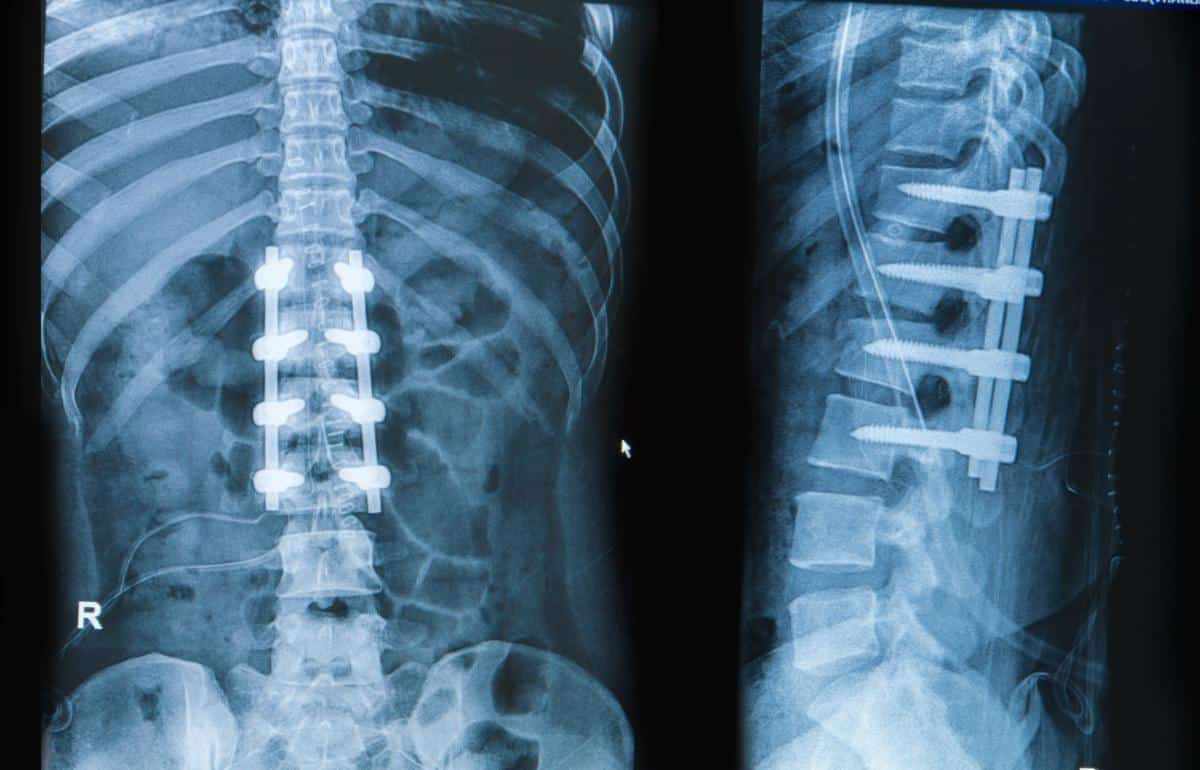

“(Spinal) Fusion is one of the most commonly performed spinal procedures, indicated for a wide range of spinal problems. Elimination of motion though results in accelerated degeneration of the adjacent level, known as adjacent level disease. Motion preservation surgical methods were developed in order to overcome this complication. These methods include total disc replacement, laminoplasty, interspinous implants and dynamic posterior stabilization systems. The initial enthusiasm about these methods was followed by certain concerns about their clinical usefulness and their results.”

In this study surgeons reassessed a few of the most commonly performed spinal fusion alternative surgical procedures. “(Motion preservation surgical methods) include total disc replacement, laminoplasty (cutting away of bone and other pressure causing material on the nerves), interspinous implants (spacers to hold nerve pathways open) and dynamic posterior stabilization systems (not a fusion but similar).”